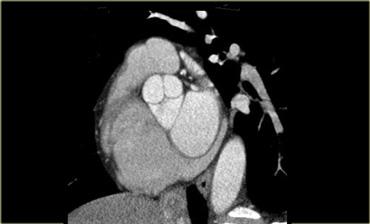

Tái tạo mặt cắt ngang (trái) và tái tạo 3D (phải) của tim cho thấy tiểu nhĩ phải (mũi tên xanh). Ao=động mạch chủ, LA=nhĩ trái

Tiểu nhĩ phải

Tiểu nhĩ phải là phần có cấu trúc bè cơ của nhĩ phải.

Nó che phủ một phần rãnh nhĩ thất và động mạch vành phải chạy trong đó.

Đặc trưng, tiểu nhĩ phải có hình dẹt và tam giác, chứa các bó cơ nhỏ chạy song song với nhĩ.